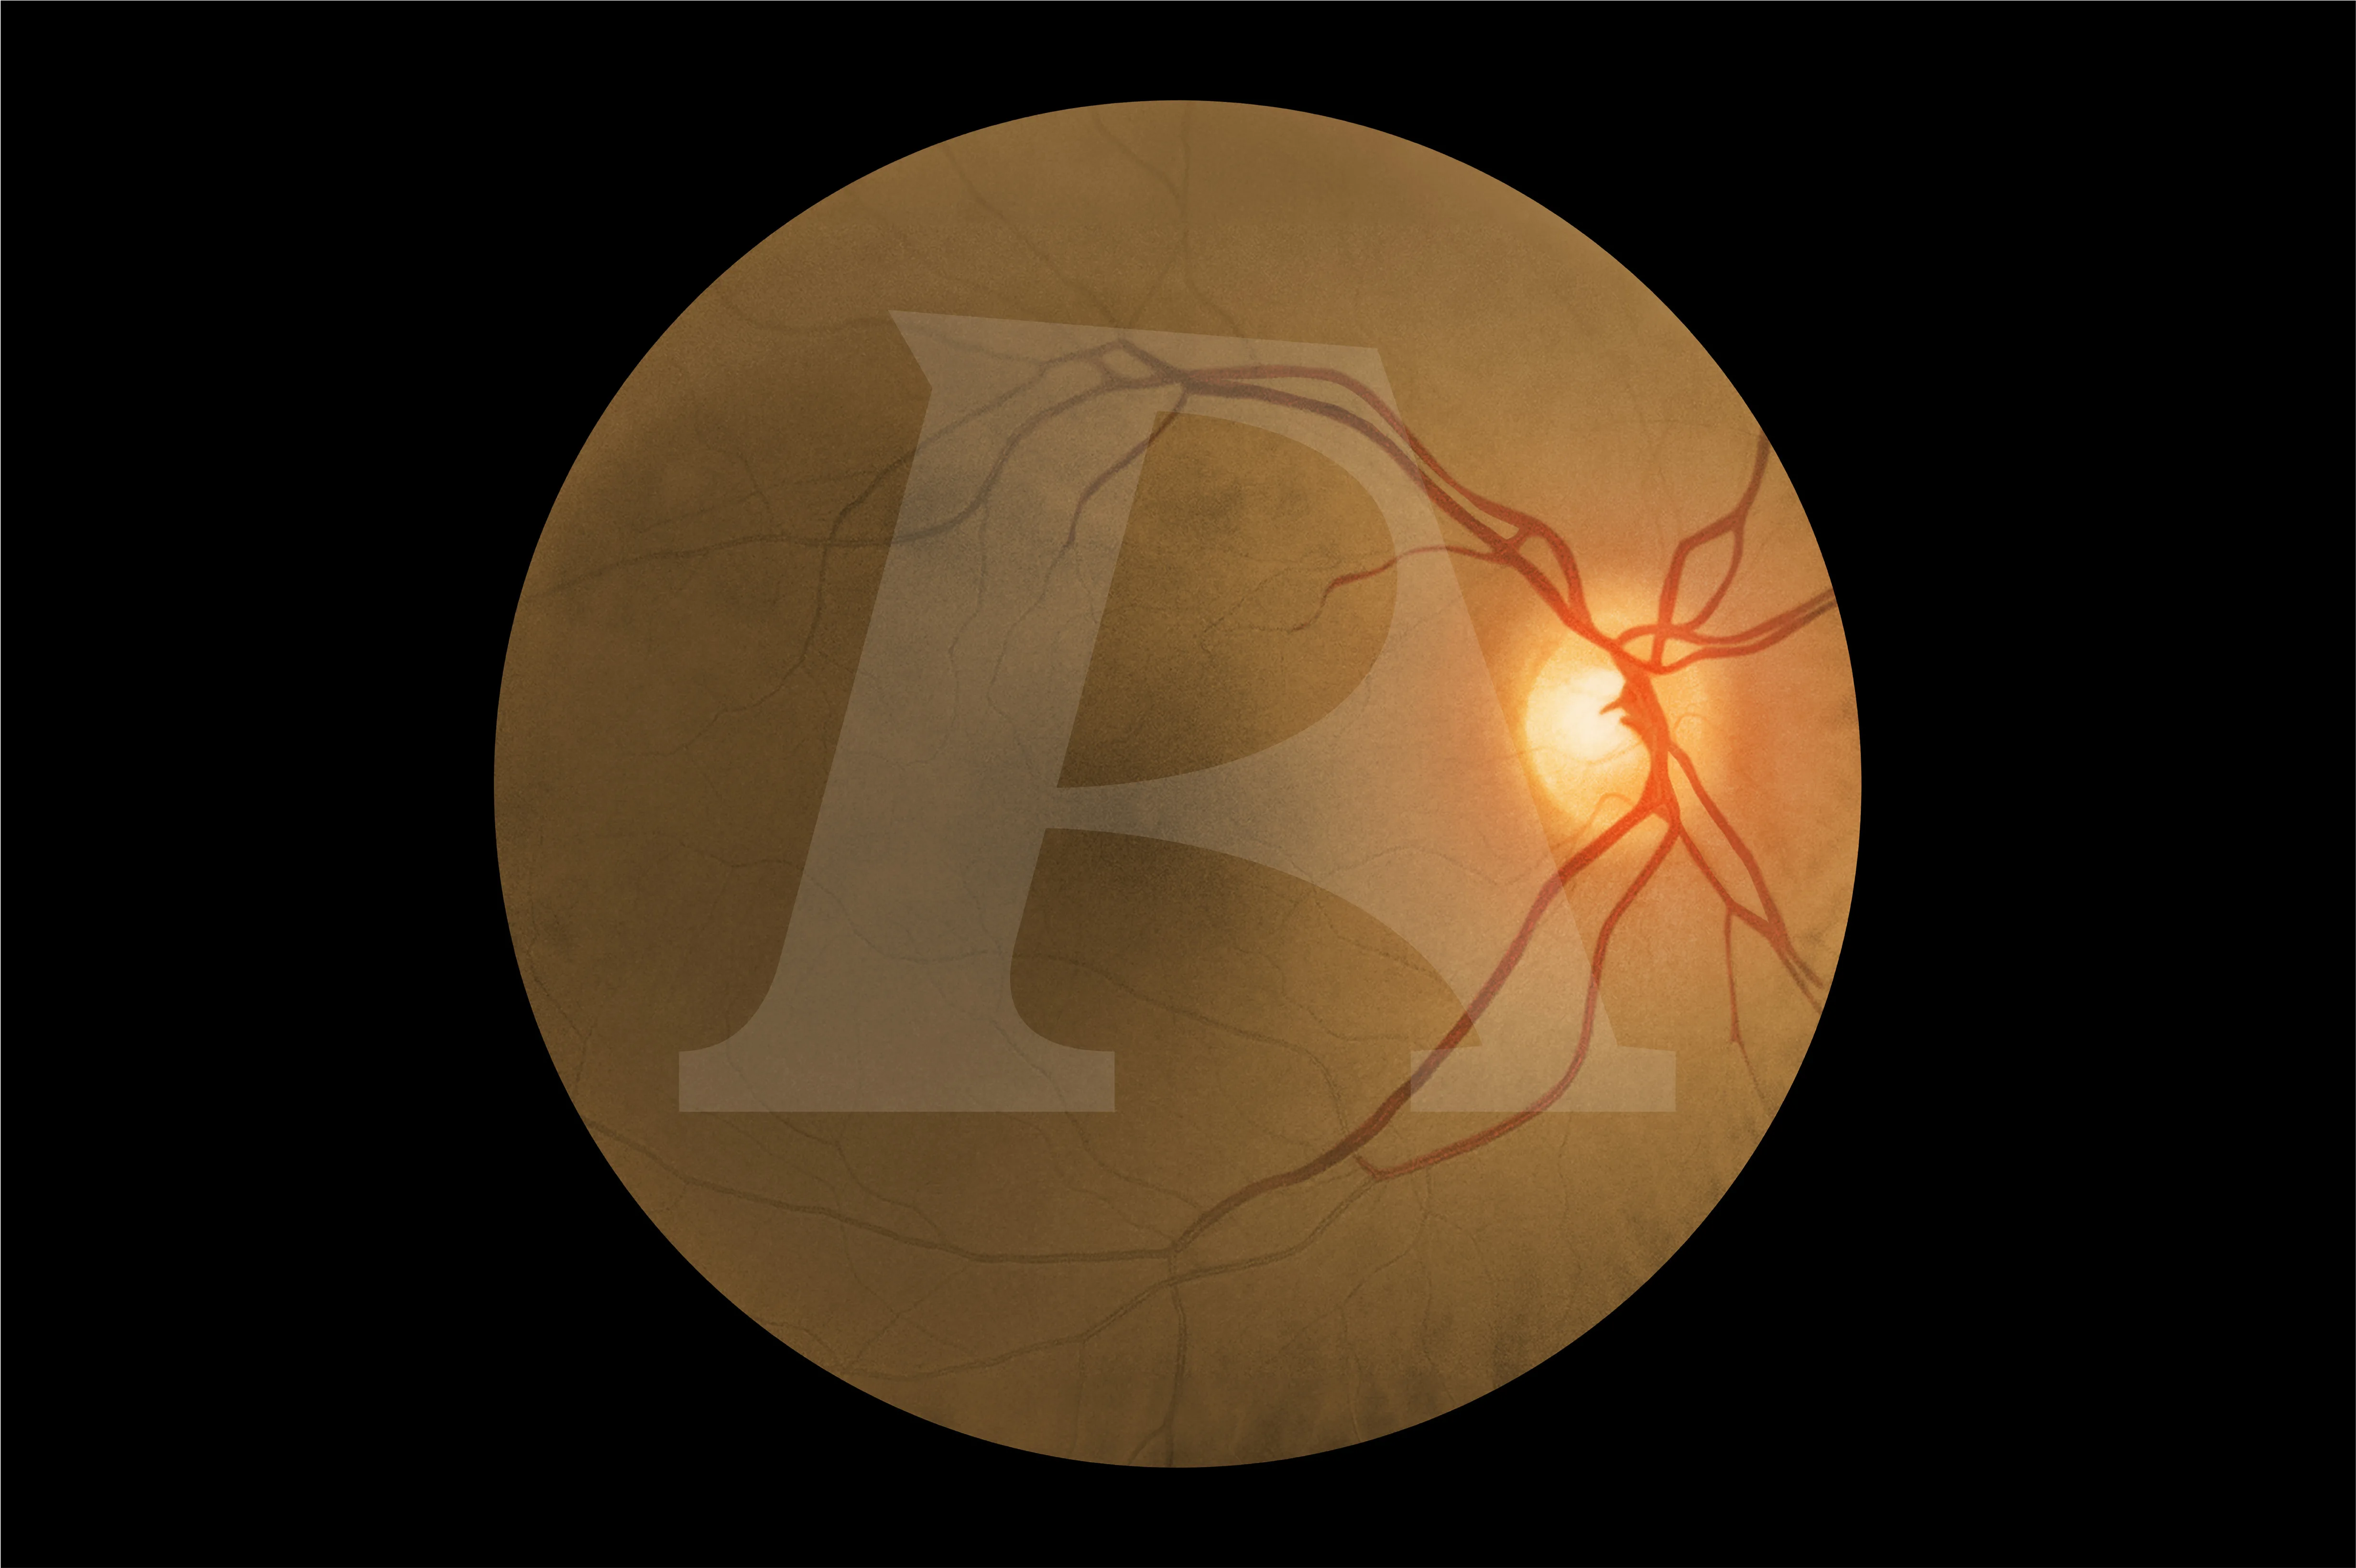

For the first time, advanced digital technology allows trainees to experience how the same eye condition can present differently in patients with light and dark skin tones. In darker-skinned patients, deeper pigmentation in the fundus reduces vessel visibility, a nuance replicated only in the AR503/50 Dark model. This provides learners with invaluable exposure to the clinical variations they will encounter in real practice, enhancing both competence and confidence. Offering two product versions enables trainees to gain an awareness of these visible variances.

Eye conditions and diseases presented digitally for the light skin toned patients AR503 and dark skin toned patients AR503/50:

Diabetic Retinopathy:

Background Diabetic Retinopathy (R1) with Maculopathy (M0)

Important / Common Retinal Conditions:

Normal Fundus (Optic Disc and Retina)